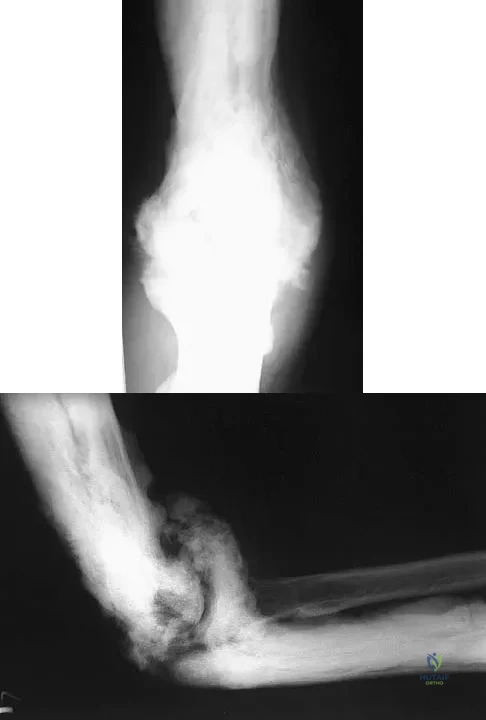

Question 11:

A 52-year-old man who was a former high school pitcher now reports loss of elbow flexion and extension with pain at the extremes of motion. Nonsurgical management has failed to provide relief. Examination reveals movement from 50 degrees to 110 degrees and is painful only at the limits of motion. A radiograph is shown in Figure 12. Treatment should consist of

Correct Answer: excision of the osteophytes and loose bodies and anterior and posterior capsular releases.

Explanation:

Based on the history, examination, and radiograph, the patient has typical degenerative arthritis of the elbow. This condition is found almost exclusively in men, and there is almost universally a history of repetitive heavy use or overuse of the elbow. Patients report pain at terminal extension and usually have a flexion contracture. Radiographs reveal osteophytes on the coronoid and olecranon and in the coronoid and olecranon fossae. The osteophytes are often associated with loose bodies that sometimes are attached to the soft tissues. Treatment should consist of removal of all loose bodies and impinging osteophytes using open technique or by arthroscopy. The capsular contractures should be released at the same time. Kasser JR (ed): Orthopaedic Knowledge Update 5. Rosemont, IL, American Academy of Orthopaedic Surgeons, 1996, pp 283-294. Morrey BF: Primary degenerative arthritis of the elbow: Treatment by ulnohumeral arthroplasty. J Bone Joint Surg Br 1992;74:409-413. Redden JF, Stanley D: Arthroscopic fenestration of the olecranon fossa in the treatment of osteoarthritis of the elbow. Arthroscopy 1993;9:14-16.